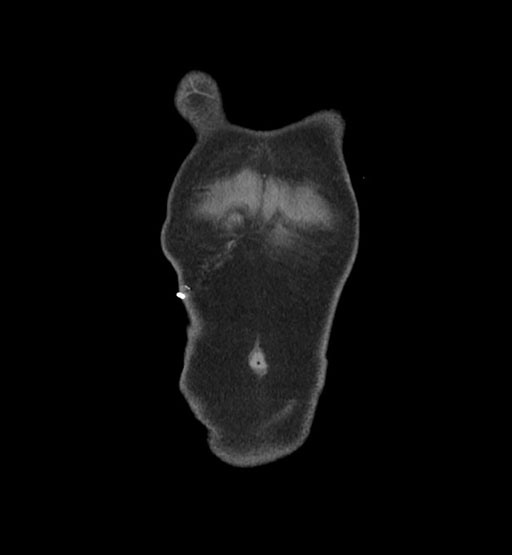

MRI T1

MRI T2